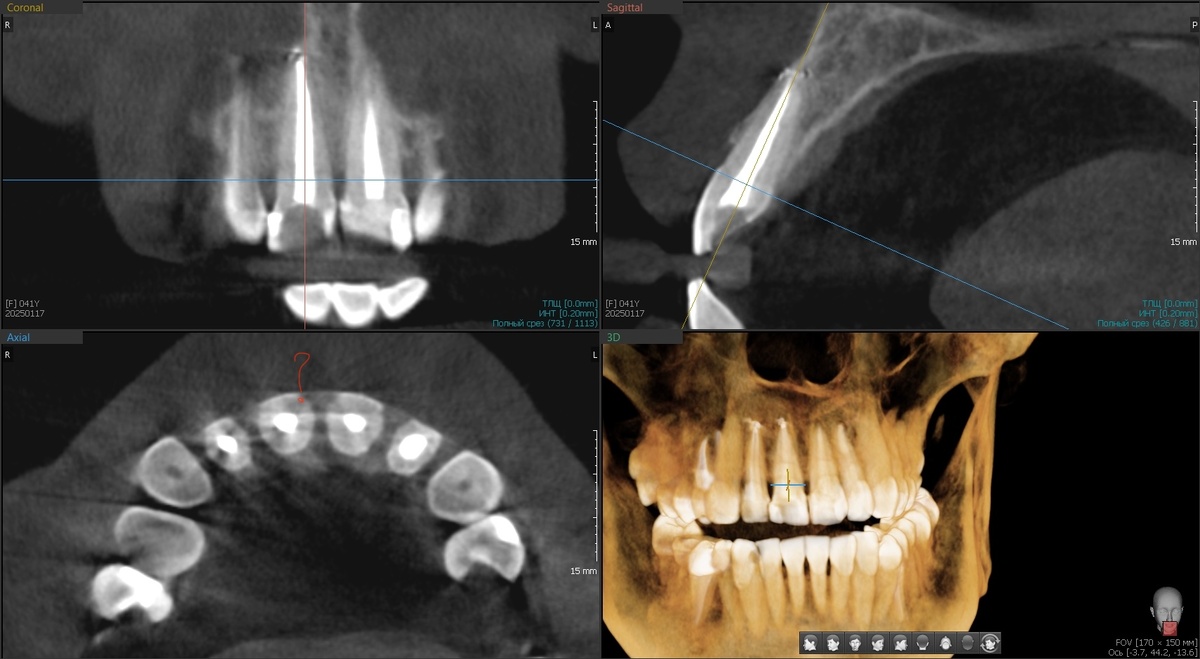

КЛКТ до попытки установить коронку

По снимку проблем не выявлено, при визуальном осмотре тоже всё хорошо. Возможно, проблема в пломбе, нужно её убирать, устанавливать временную коронку и наблюдать за ощущениями.